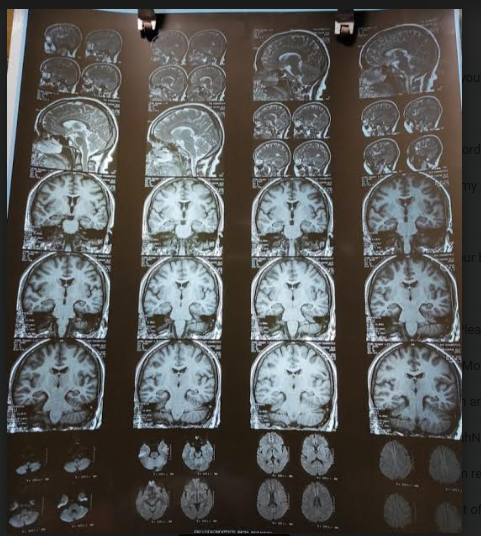

MRI Brain (P+C) showed pituitary gland enlarged with convex superior margin. Enlarged pituitary measured about 11mm in AP, 14mm in lateral and 11mm in cranio-caudal dimensions. Post contrast study showed enhancement there. Infundibulum was central. Radiologist gave impression that MRI findings are suggestive of pituitary macroadenoma.

Thus with Cabergoline, the symptoms of hyperprolactinemia resolved and the tumour size markedly regressed Figures 1–4.

Figure 1 MRI brain of the patient.